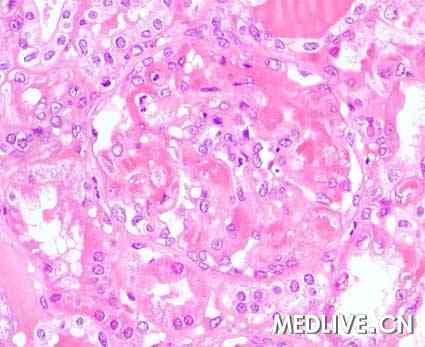

肾活检图片如图。

图2 HE染色 200×

临床诊断:血栓性微血管病(起源于供体)

血栓性微血管病(Thrombotic microangiopathy, TMA)定义为毛细血管和(或)小动脉内血栓形成。TMA是公认的严重肾移植术后并发症之一。该病血管内溶血的临床特点并不总表现出来。该病分为新发TMA和复发TMA,多数新发TMA与环孢菌素治疗有关。病毒感染、严重肾缺血和急性血管性排斥反应是较少见原因。

肾小球毛细血管或小动脉内纤维性血栓形成可用于诊断血栓性微血管病。全身性TMA诊断依据是出现血小板减少和微血管病性溶血的证据。本例中活检结果与血栓性微血管病特征一致,但是无任何全身性溶血改变者考虑有局部TMA。